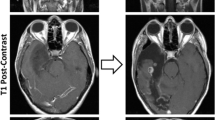

Our total cohort was composed of 148 tumor samples from 144 patients (Supplemental Table 2). The mean and median age of patients at the time of surgery were 44 years and 43 years (range 4–88 years), respectively. Of the 135 patients with known age at time of diagnosis, 12 (8.9%) were in the pediatric age group (< 18 years) (Supplemental Table 2). Tumors occurred in 59 female and 85 male patients (ratio 1:1.44). Disease stage included 74 primary tumors, 38 recurrent tumors, and 36 tumors with unknown designation. Tumor location was known for 130 patients, with 81 located in the posterior fossa, 34 located in the supratentorial region, and 13 in the spinal cord. Histopathology on available cases included glioblastoma-like histomorphology (Fig. 1a–f) and most with an infiltrative growth pattern, in 26 of the 30 (86.7%) evaluable cases. The presence of necrosis and/or microvascular proliferation was observed in 38 of 61 (62.3%) HGAP tumors. The piloid-associated features of Rosenthal fibers and/or eosinophilic granular bodies were present in a minority (23 of 61; 37.7%). Mitotic activity was variable, ranging from 0 to 6 mitoses/mm2. Similarly, the maximum Ki-67 proliferative index had a broad spectrum, ranging 1–30%.

Several clinical features beyond NF1 status tended to differ across HGAP subtypes. The initial tumors of gNF1, g1, and g2 subtypes had median ages of 43.5 years, 47.0 years, and 32.0 years, respectively (p > 0.05 for all pairwise comparisons, Mann–Whitney U tests, Fig. 4a, b). Only one of the twelve pediatric tumors was gNF1 subtype (Supplemental Table 2). Tumor localization varied among the three HGAP subtypes, with gNF1 having 100% of the tumors located in the posterior fossa (Fig. 4c, d). By contrast, subtypes g1 (35.4% supratentorial, 55.4% posterior fossa, 9.2% spinal cord) and g2 (29.2% supratentorial, 56.2% posterior fossa, 14.6% spinal cord) were found throughout the neuraxis (Fig. 4d). While HGAP subtype was associated with tumor location (chi-square, **p = 0.001) the significance was less than that of subtype association with NF1 syndrome. Furthermore, no association was observed between tumor location and NF1 syndrome (p = 0.359). Tumor location itself was not associated with difference in survival (Supplemental Fig. 3). Progression-free survival trended towards worse outcome for the gNF1 subtype when compared to the other two subtypes (Fig. 4e, f). The gNF1, g1, and g2 subtypes had median progression-free survival times of 252 days, 565 days, and 618 days, respectively. Overall survival appeared similar among all subtypes, although the number of patients with overall survival data was low (Fig. 4g, h). Three of the patients had recurrent tumors, all of which maintained their subtype assignment when compared to their original tumor. The first of these three patients had known Neurofibromatosis Type 1, with their original and two recurrent HGAPs all belonging to the gNF1 HGAP subtype. The other two patients did not have a clinical diagnosis of Neurofibromatosis Type 1. The second patient had paired initial and recurrent HGAP tumor in the g1 subtype while the third patient had paired initial and recurrent HGAP tumor in the g2 subtype.